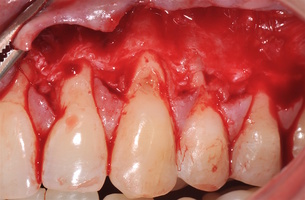

1. Генерализованные рецессии в области нижней челюсти оперировались в один этап все 12 зубов, фронтальный участок с аутотрансплантатом от 3.2 до 4.2 зубов. А дистальные участки от 3.6 до 3.3 и от 4.6 до 4.3 зубов с использованием пластического материала ТМО (dura mater) (рис. 4а-з).

4. Этапы хирургического лечения рецессий десны на нижней челюсти

3.2-4.2 зубы были прооперированы методом, сочетающим вестибулопластику с одновременным увеличением ширины и толщины прикрепленной десны при помощи свободного десневого аутотрансплантата (операция Bjorn, 1963 г.).

1. Подготовка принимающего ложа. Включает в себя формирование полнослойно-расщепленного слизисто-надкостничного лоскута (полнослойного в области зенитов рецессий, расщепленного билатерально области рецессии десны), рассечение и отслаивание слизисто-мышечных волокон вестибулярно ниже мукогингивальной границы, деэпителизация межзубных сосочков.

2. Обработка поверхностей корней зубов. Включает ультразвуковую обработку скейлером для очищения от минерализованных зубных отложений и мягкого зубного налета, экспозицию геля ЭДТА 17% в течение двух минут, механическое удаление слоя бесклеточного цемента импрегнированного микроорганизмами зоноспецифическими кюретами, полировку пародонтологическими борами («фасолька» и «обратный треугольник»).

3. Получение аутотрансплантата: начинается с определения толщины донорской зоны и замеров размера будущего трансплантата. Зона забора от второго премоляра до третьего моляра верхней челюсти. Глубина погружения брюшка скальпеля 2 мм, далее трансплантат оптимизируют — деэпителизируют по периметру.

4. Затем проводиться позиционирование аутотрансплантата в области рецессий и принимающего ложа двумя-тремя узловыми швами; после аутотрансплантат стабилизируют прижимающими двумя-четырьмя матрасными крестообразными швами, что позволит плотно прижать аутотрансплантат и избежать образования «мертвых» зон для питания аутотрансплантата.